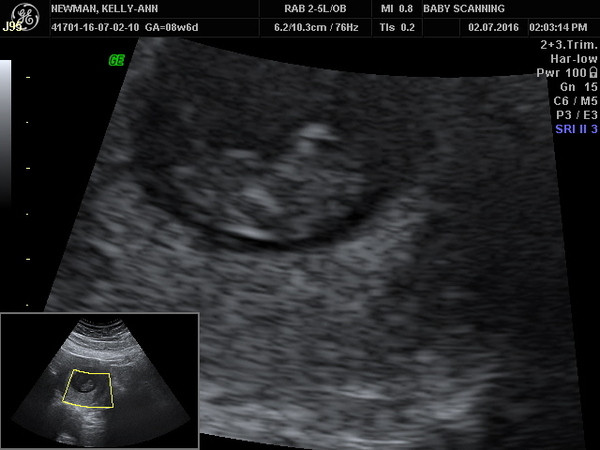

LondonGirl83 · 02/07/2016 22:02

here is the scan pic finally!

Aww lovely london SmileSmileSmile